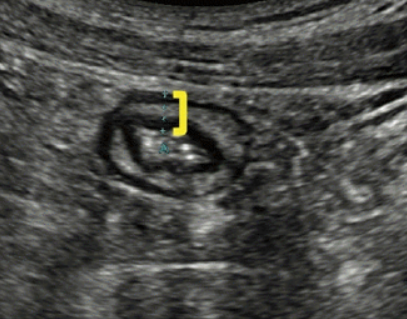

Keyboard sign

Intussusception